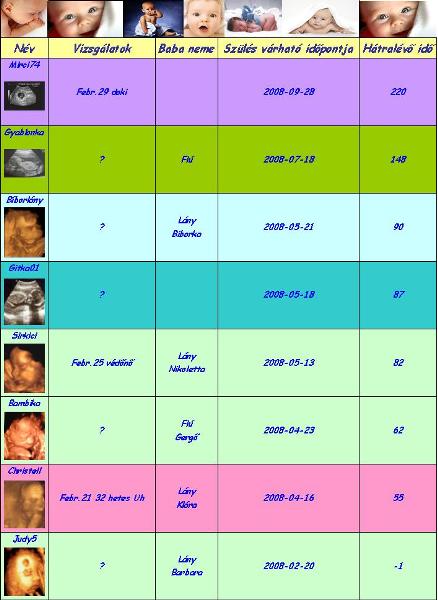

Az uh-n minden rendben volt, hallgattuk a szivhangot, vagy nem is tudom, szerintem az volt, hogy a köldökzsinórban keringett a vér és annak a hangja volt, a súlya 1262 g, szerintem az elég sok igy 28 hetesen, de nemtudom honnan tudnám ezt megnézni, meg farfekvéses még mindig a kincsem, de a doki azt mondta, hogy van még ideje megfordulni, remélem meg fog. Ééééééééééés a lényeg, hogy a doki szerint 100 %-ig biztos, hogy KISLÁNY! Hát nemtudom, én még mindig nem tudom elhinni, de kaptunk róla képet, majd otthon beszkennelem, és felteszem, hátha valaki ért hozzá?!

Mutogatta a három vonalat, és meg is kérdezte apától, hogy látja apuka?! Szegény apa mondta, hogy látja, de mit is kell nézni, és akkor elmagyarázta a doki, hogy ez a három vonal a bizonyiték a kislányra, hogy nem hazudik...

Judy,

úgy látszik Barbika nagyon jól érzi magát odabenn!